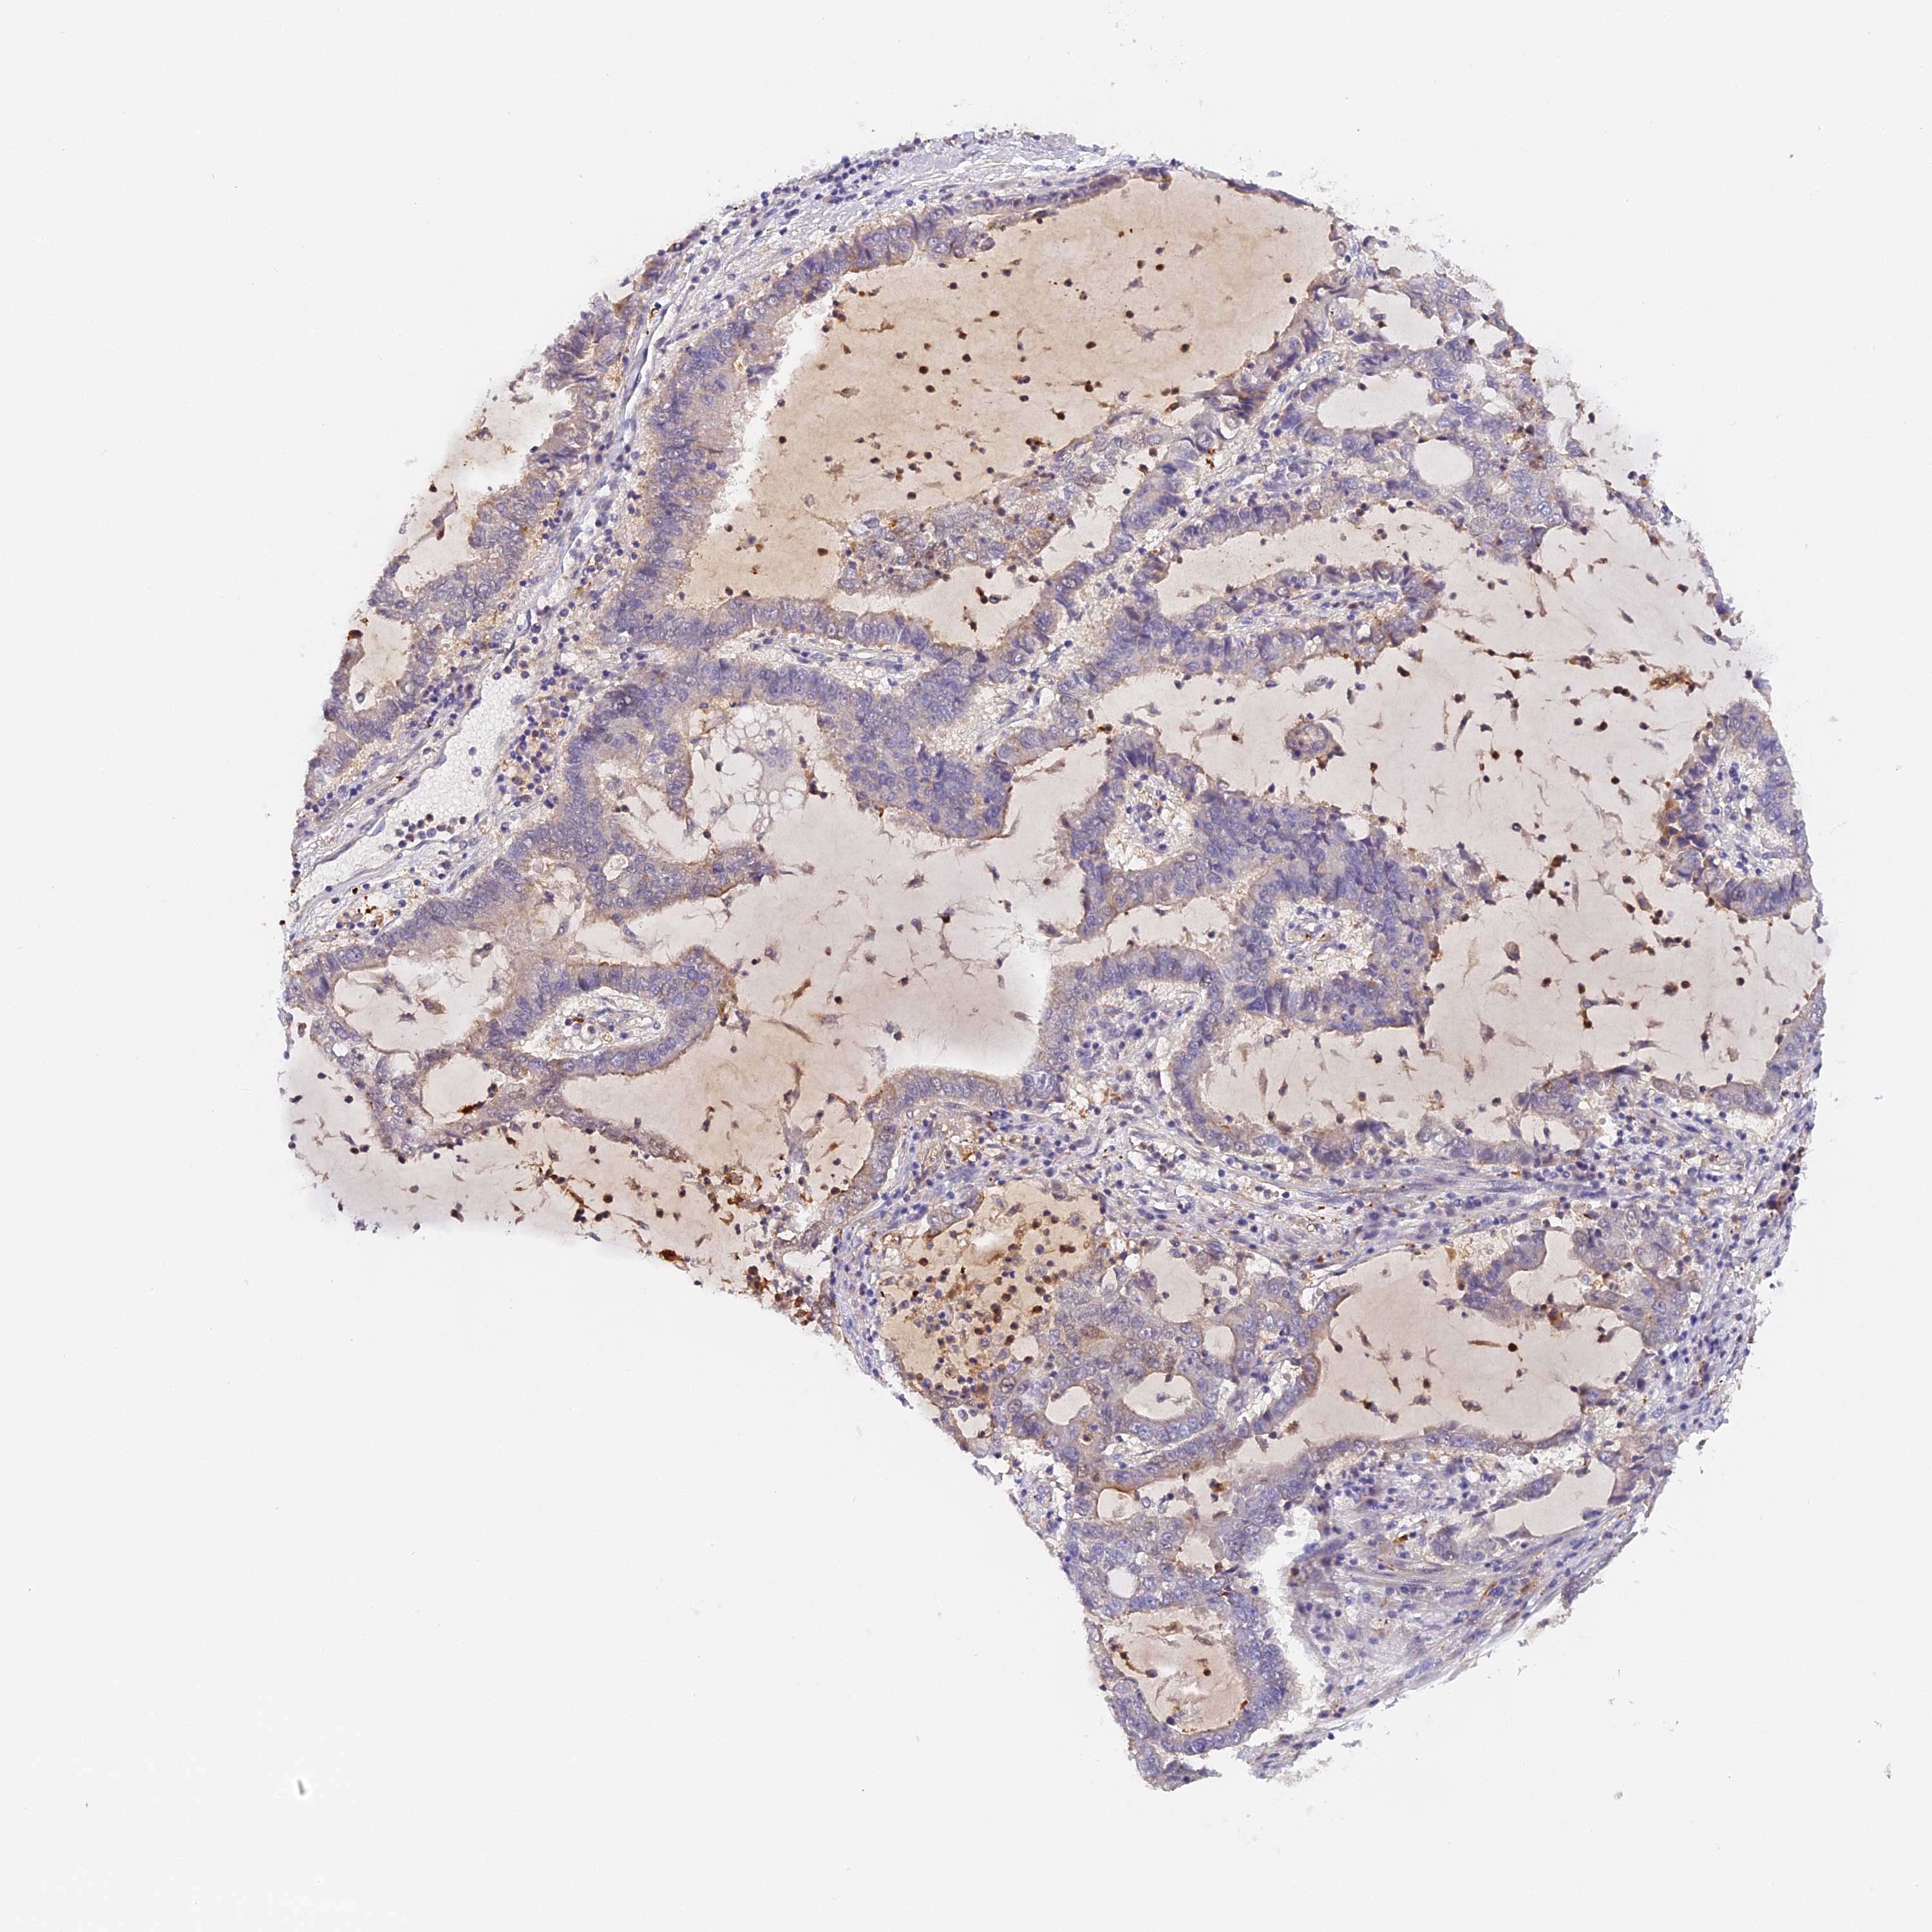

LUNG SQUAMOUS CELL CARCINOMA (TCGA) - Interactive survival scatter ploti

The Survival Scatter plot shows the clinical status (i.e. dead or alive) for all individuals in the patient cohort, based on the same data that underlies the corresponding Kaplan-Meier plots. Patients that are alive at last time for follow-up are shown in blue and patients who have died during the study are shown in red.

The x-axis shows the expression levels (FPKM) of the investigated gene in the tumor tissue at the time of diagnosis. The y-axis shows the follow-up time after diagnosis (years). Both axes are complimented with kernel density curves demonstrating the data density over the axes. The top density plot shows the expression levels (FPKM) distribution among dead (red) and alive patients (blue). The right density plot shows the data density of the survived years of dead patients with high and low expression levels respectively, stratified using the cutoff indicated by the vertical dashed line through the Survival Scatter plot. This cutoff is automatically defined based on the FPKM cutoff that minimizes the p-score. The cutoff can be changed by dragging the vertical line or by entering a cutoff value in the square labeled "Current cut-off".

Under the Survival Scatter plot the p-score landscape (black curve; left axis) is shown together with dead median separation (red curve; right axis). Dead median separation is the difference in median mRNA expression between patients who have died with high and low expression, respectively. It is calculated as follows: median FPKM expression of dead patients with high expression - median FPKM expression of dead patients with low expression. This is intended to aid the user in visually exploring custom cutoffs and the associated p-scores and dead median separation.

Individual patient data is displayed and can be filtered by clicking on one or more of the category buttons on the top of the page. Categories describing expression level and patient information include: high, low, alive, dead, female, male and tumor stages. The scale of the x-axis can be toggled between linear and log-scale by clicking on the "x log" button. Mouse-over function shows TCGA ID, patient information and mRNA expression (FPKM) for each patient.

& Survival analysisi

Kaplan-Meier plots summarize results from analysis of correlation between mRNA expression level and patient survival. Patients were divided based on level of expression into one of the two groups "low" (under cut off) or "high" (over cut off). X-axis shows time for survival (years) and y-axis shows the probability of survival, where 1.0 corresponds to 100 percent.

KATNB1 is not prognostic in Lung Squamous Cell Carcinoma (TCGA)

: 16.22

Average pTPM 20.3

Number of samples 489